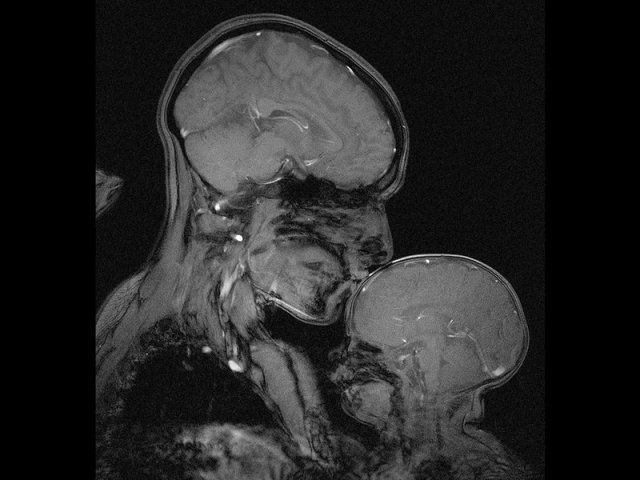

ANATOMY OF A MURDERER: Homicide offenders exhibited reduced gray matter density compared with other violent offenders in the regions of the brain highlighted blue and green above.